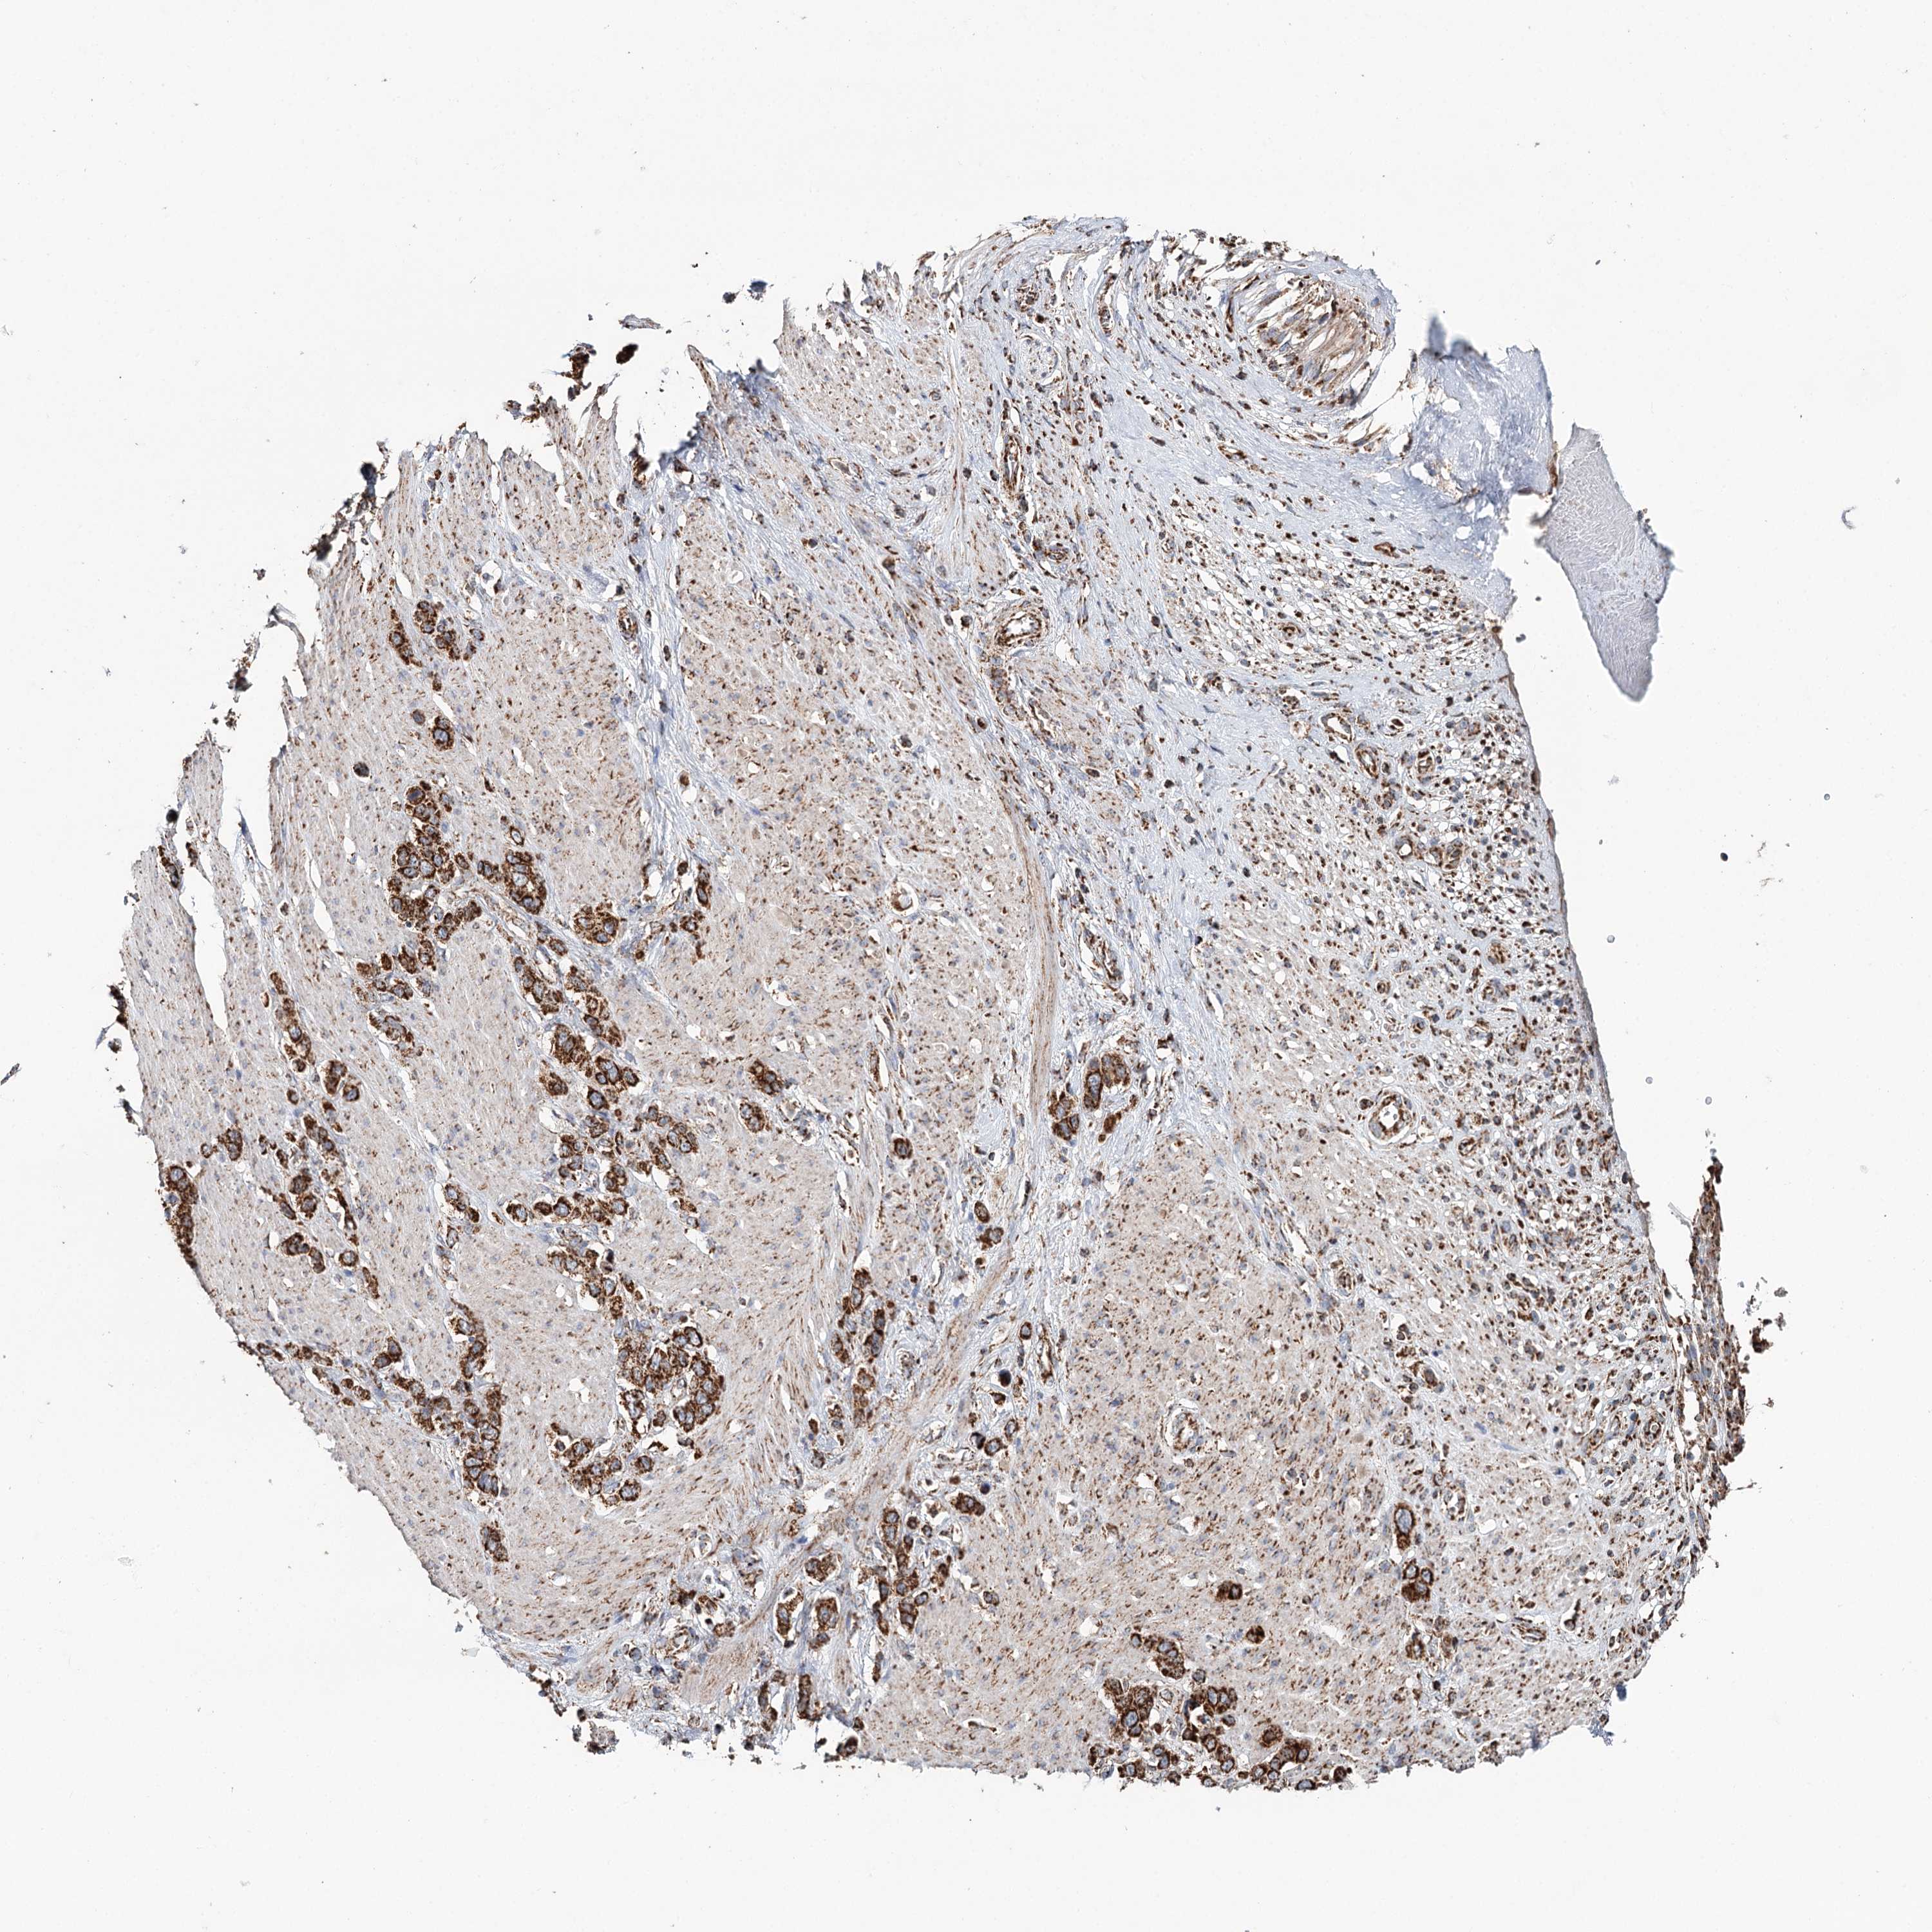

STOMACH CANCER - Protein expressioni

A mouse-over function shows sample information and annotation data. Click on an image to view it in a full screen mode. Samples can be filtered based on level of antibody staining by selecting one or several of the following categories: high, medium, low and not detected. The assay and annotation is described here.

Antibody stainingi

Antibody staining in the annotated cell types in the current human tissue is reported as not detected, low, medium, or high, based on conventional immunohistochemistry profiling in selected tissues. This score is based on the combination of the staining intensity and fraction of stained cells.

Each image is clickable and will lead to virtual microscopy that enables deeper exploration of all samples and also displays staining intensity scores, fraction scores and subcellular localization as well as patient and tissue information for each sample.

Antibody CAB037272

Staining

High

Medium

Low

Not detected

Intensity

Strong

Moderate

Weak

Negative

Quantity

>75%

75%-25%

<25%

None

Location

Nuclear

Cytoplasmic/membranous

Cytoplasmic/membranous,nuclear

Adenocarcinoma, NOS